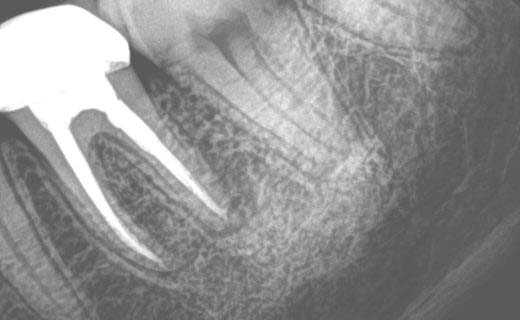

Do you need a root canal in NYC? Don’t be nervous; 209 NYC Dental will walk you through every step. Schedule your appointment now and let us alleviate your discomfort with ease. Our root canal specialists employ the benefits of cutting-edge dental technology, including digital X-rays and high-powered microscopes, to achieve the best results & maximum precision in NYC root canal treatments.

Each member of our stellar endodontic team is highly trained in advanced root canal therapy, ensuring that every patient receives gentle, effective, and long-lasting care. Whether you need a root canal for a sudden dental problem or a long-standing issue, our specialists will identify the problem quickly using advanced diagnostics that include 3D cone beam imaging.

Because our root canal specialists use cutting-edge technology to perform procedures, they’re able to detect even the smallest canal branches that the naked eye could easily miss. This level of precision helps prevent our patients from reinfections and improves their long-term outcomes.